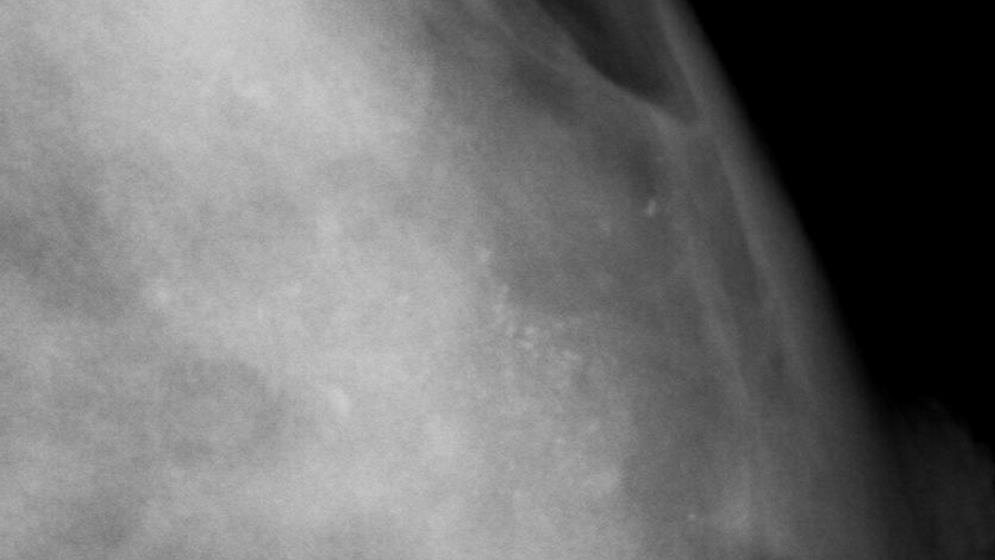

Eine aktuelle Studie zeigt: Selbst wenn nach der Mammographie-Screening-Untersuchung innerhalb der nächsten zwei Jahre ein Tumor entdeckt wird, befindet sich die Erkrankung seltener in einem ungünstigen, fortgeschrittenen Stadium.

Bei der Auswertung von rund 19.500 Erstteilnehmerinnen und 18.000 wiederholt teilnehmenden Frauen in Nordrhein-Westfalen zeigen sich deutliche Vorteile für die zweite Gruppe. Von 1.000 Frauen, die erstmals eine Mammographie-Screening-Untersuchung durchgeführt haben, wurde innerhalb von zwei Jahren bei etwa 13 Frauen Brustkrebs entdeckt. Dabei sind auch die Frauen erfasst, die erst nach der Screening-Untersuchung in den darauf folgenden zwei Jahren (im Intervall) erkrankt sind. Bei rund 5 Frauen war der Krebs in einem fortgeschrittenen Stadium.

Bei Frauen, die bereits wiederholt am Screening teilnahmen, wurde Brustkrebs bei etwa 9 von 1.000 Frauen gefunden. Bei rund 2 bis 3 der Frauen war der Tumor entweder größer als 2 Zentimeter und/oder wies eine Metastasierung auf (fortgeschrittene Erkrankung).

"Wir können mit dieser Studie erstmals in Deutschland zeigen, dass Frauen nach wiederholter Teilnahme am Mammographie-Screening auch dann einen Vorteil haben, wenn zwischen den zweijährlichen Screening-Untersuchungen der Brustkrebs auftritt", sagt Prof. Walter Heindel, Leiter des Referenzzentrums Mammographie am Universitätsklinikum Münster und einer der Studienautoren. Der Anteil der fortgeschrittenen Stadien war für diese Frauen nur etwa halb so hoch wie für die Frauen, die erstmals an der Screening-Untersuchung teilnahmen. "Wir finden nicht nur Brustkrebs in einem frühen Stadium, sondern können gleichzeitig durch die regelmäßige Untersuchung den Anteil der fortgeschrittenen Stadien verringern. Damit kann es gelingen, in den nächsten Jahren die Sterblichkeit an Brustkrebs durch Screening weiter zu senken." (ots, red)